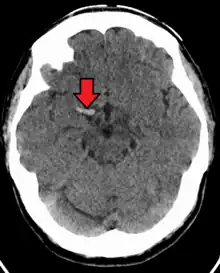

Acute thrombus in the right MCA M1 branch

A stroke is the rapid decline of brain function due to a disturbance in the supply of blood to the brain.[12] This can be due to ischemia, thrombus, embolus (a lodged particle) or hemorrhage (a bleed).[12] In thrombotic stroke, a thrombus (blood clot) usually forms around atherosclerotic plaques. Since blockage of the artery is gradual, the onset of symptomatic thrombotic strokes is slower. Thrombotic stroke can be divided into two categories — large vessel disease or small vessel disease. The former affects vessels such as the internal carotids, vertebral and the circle of Willis. The latter can affect smaller vessels, such as the branches of the circle of Willis.